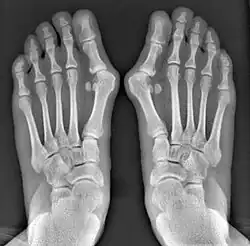

Fig. 8a. Painful hallux valgus and metatarsus primus varus deformity recurrence of left foot after osteotomy surgery

1. For recurrence correction after osteotomy procedure (Fig. 8)

Late deformity recurrence can happen after osteotomy (bone-breaking) procedures because osteotomy surgeries do not specifically stabilize first metatarsal bone.